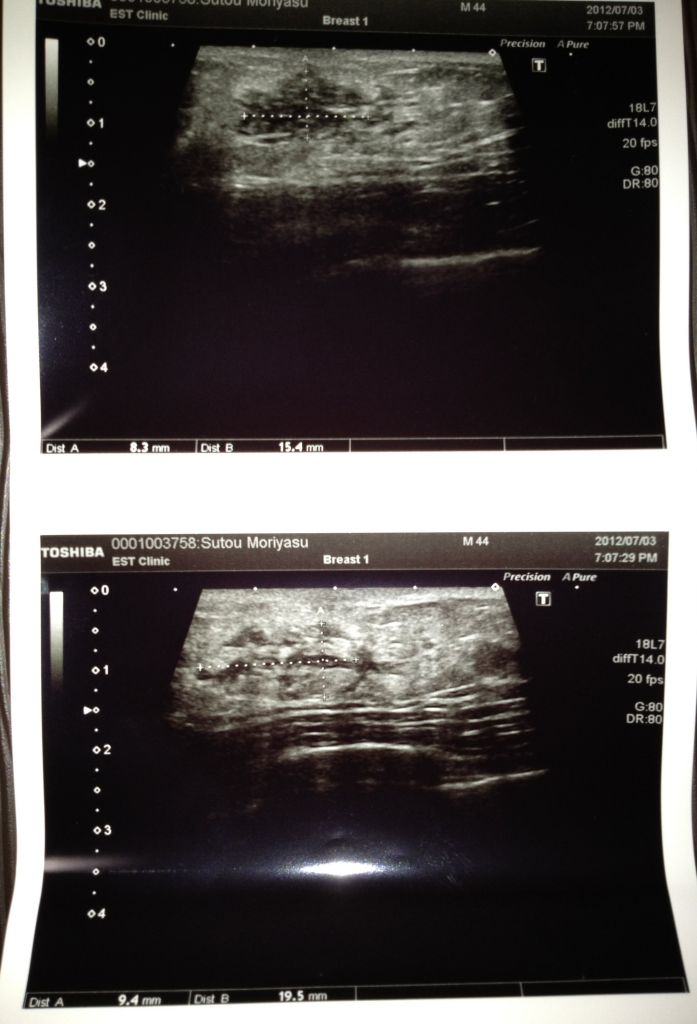

1ヵ月に一回通っている病院へ行ってきました

今日は

ちょっと心配なコトがあり

先生に相談してみました

その・・・心配なコトって

実は

私の右側の乳房に

シコリみたいなものがあって・・・・・

当たるとちょっとだけ痛いんです

男で乳癌はありえないとは思ったのですが

いつもの内科の先生は

「これは、女性化乳房だと思われます

一応、外科の先生にも診てもらいましょう・・・」って

次に

外科へ行ったら

外科の先生も

乳房を揉みながら

「女性化乳房だと思いますが、一応検査します」

ここの病院はマンモグラフィーって機械がないらしく

エコーで調べると言う

検査室へ行って

若い女性スタッフに

「上を脱いで・・・」って

右の乳房にゼリー状のものを塗られました

外科の先生がエコーの機械を動かして調べてくれて

私に説明してくれました

「この黒く見えるのがシコリで、癌ならもっとギザギザに見えます」とのコト

そんなに心配はしてなかったケド

安心しました

最後に

「もし、シコリが大きくなったり痛みが出たらスグ来て下さい」と言われました